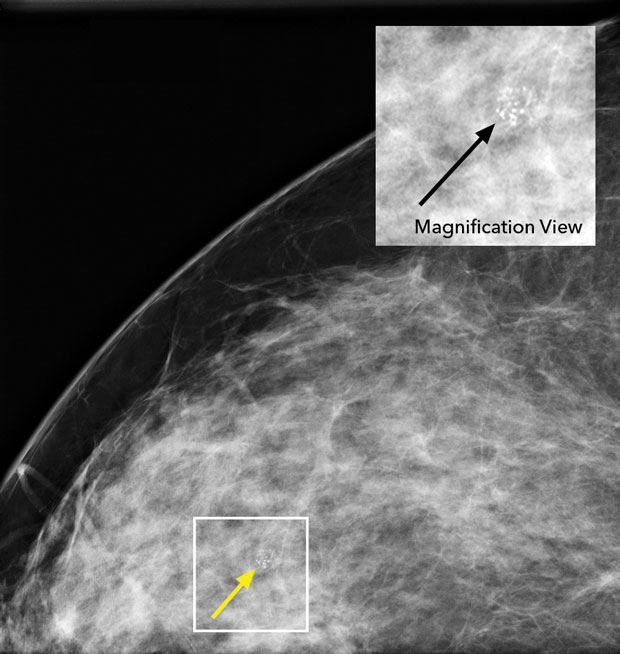

No additional treatment (Option D) is indicated for this patient. Ductal carcinoma in situ (DCIS) is a noninvasive breast cancer that usually presents as calcifications on mammography, as shown in the image to the right. DCIS can evolve into invasive breast cancer, and therefore the treatment goal is to eradicate the area of DCIS and decrease the risks for local recurrence and death from invasive breast cancer. Local treatment involves either lumpectomy, sometimes followed by radiation therapy, or mastectomy. Postlumpectomy radiation therapy improves disease-free survival but not breast cancer–specific mortality and can be omitted in some cases, especially in patients with small, low-risk DCIS. Adjuvant endocrine therapy with aromatase inhibitors or tamoxifen can be considered in those with DCIS to prevent locoregional recurrences and decrease the risk for a second primary breast cancer. Endocrine therapy is indicated to improve recurrence-free intervals in patients with estrogen receptor– and/or progesterone receptor–positive DCIS (90% of cases) who underwent local excision. In a patient who has undergone bilateral mastectomy for DCIS, however, there is no role for endocrine therapy. This patient underwent mastectomy for DCIS, and no adjuvant therapy is indicated.